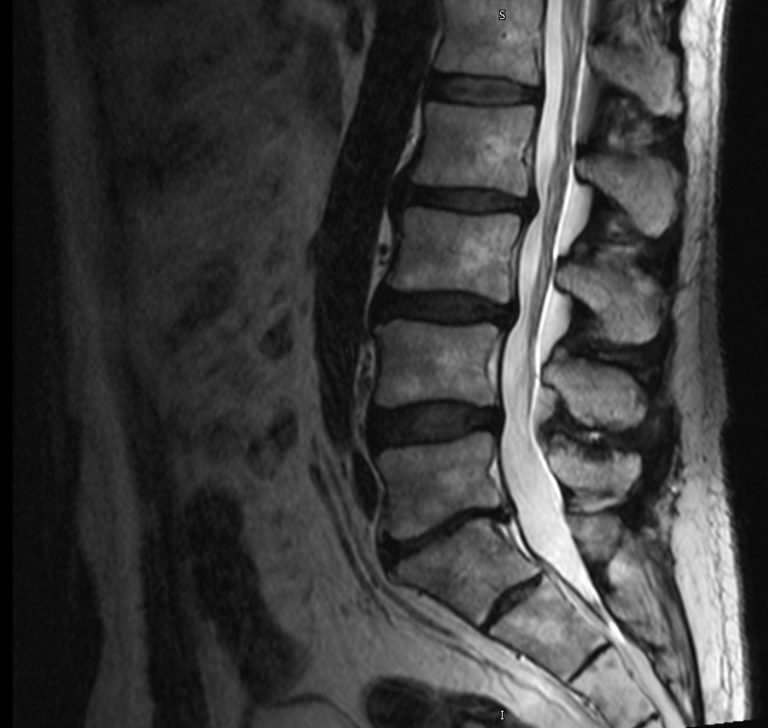

Despite being a safe operation with several benefits, there are some risks that come with lumbar disc replacement. The lumbar spine is made up of the 5 vertebral bones and intervertebral discs between the rib cage and the pelvis. Every patient is different and your doctor will walk you through. Disc replacement removes a damaged spinal disc and replaces it with an artificial disc. Additional risks with cervical disc replacement are: Temporary difficulty swallowing temporary loss of voice. In lumbar artificial disk replacement, worn or damaged disk material between the small bones in the spine (vertebrae) is removed and replaced with a prosthetic, or artificial disk. Additional risks with lumbar disc. Your surgeon may recommend this surgery if you have back pain due to one or. In a study of 946 patients who went through lumbar total disc replacement, satisfaction rates ranged from 75.5% to 93.3%.

Is Lumbar Disc Replacement Safe . Your surgeon may recommend this surgery if you have back pain due to one or. Overall, this is good news for patients who. Hss research suggests that patients with greater height in their spinal discs may be better candidates than those with less disc height. In a study of 946 patients who went through lumbar total disc replacement, satisfaction rates ranged from 75.5% to 93.3%. The lumbar spine is made up of the 5 vertebral bones and intervertebral discs between the rib cage and the pelvis. Every patient is different and your doctor will walk you through. In lumbar artificial disk replacement, worn or damaged disk material between the small bones in the spine (vertebrae) is removed and replaced with a prosthetic, or artificial disk. Additional risks with lumbar disc. Patients with diseased discs in the cervical or lumbar spine who have good spinal motion and little or no arthritis are excellent candidates for disc replacement surgery. Temporary difficulty swallowing temporary loss of voice. Despite being a safe operation with several benefits, there are some risks that come with lumbar disc replacement. Disc replacement removes a damaged spinal disc and replaces it with an artificial disc. Additional risks with cervical disc replacement are: